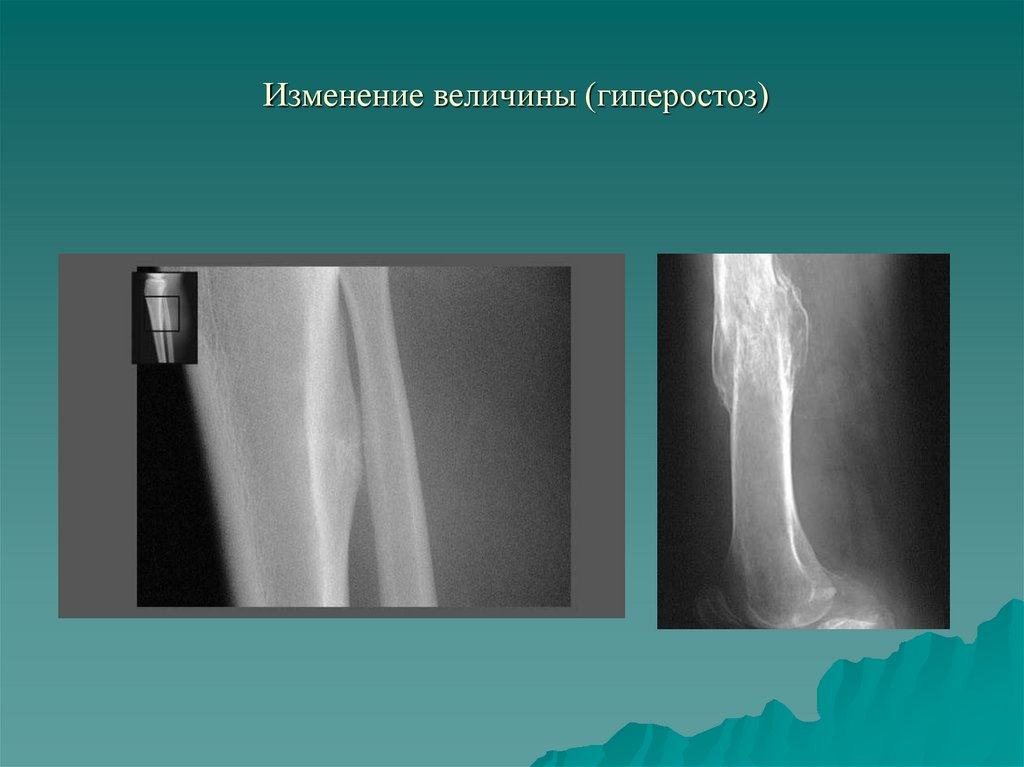

Изменение величины (гиперостоз)

4. I. Изменение величины и формы кости. Изменение количества

1.3. Утолщение кости - гиперостоз.

- Функциональный (рабочая гипертрофия);

- Воспалительный;

- Репаративный;

- Гормональный;

- Токсический (фосфор мышьяк);

- Врожденный (мелореостоз, гигантизм)

9. Изменение величины (гиперостоз)

10. Изменение величины (гиперостоз)